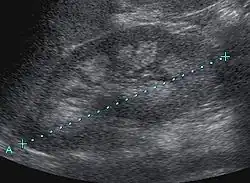

Medullary nephrocalcinosis

Medullary nephrocalcinosis in sonography